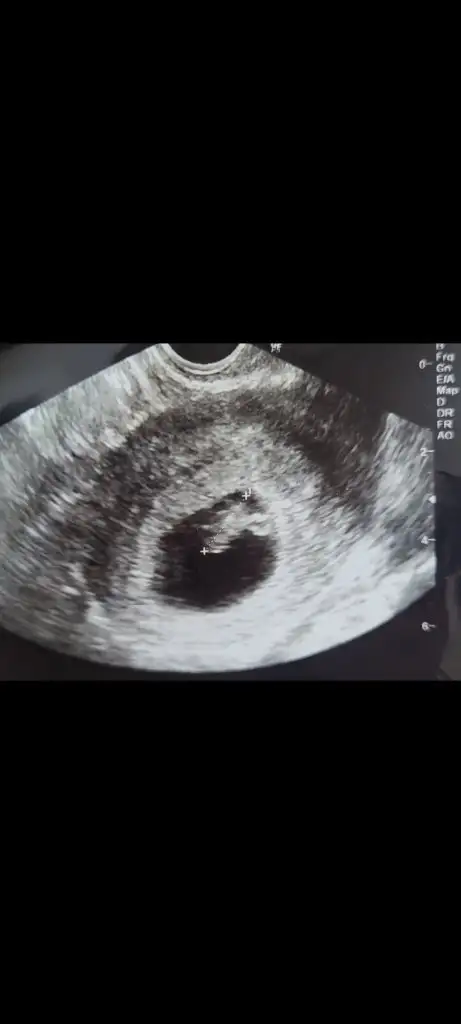

Çok teşekkür ederim.🥰 Eller kollar hareketlenmiş bir de. Öyle görünce içim kıpır kıpır oldu.Bir kızım var bir de oğlum olsun isterim.Ama kız olursa da cok mutlu olurum.Gercekten hiç fark etmez. Evlat sonuçta Rabbim hayırlısı neyse sağlıklı bir şekilde onu nasip eder inşallah.Kızıma hamileyken rüyamda kız olacağını görmüştüm.Bunda bebek gördüm ama cinsiyetini görmedim.@lolaylty 6+1 ve 7+1 ultrason görüntüsüne göre erkek demişti siz de kız dediniz.Hangisi olacak bakalım 😄 Hayırlısı olsun.Rabbim sizin bebeğinizi de gönlünüze göre sağlıklı bir sekilde kucağınıza almayı nasip eder inşallah.🙏💞